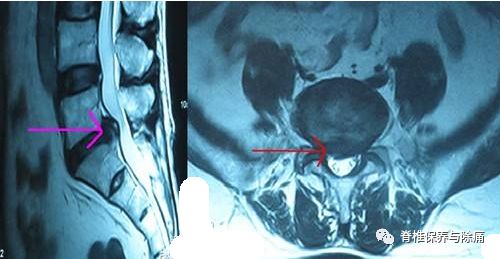

术前症状侧的神经根的轴位MRI和CTM扫描,根据严重程度病理程度分为四级0级:没有神经根受压(根映像是可视化); I级:神经根被激惹;II级:神经根移位或变形;III级:确定的神经根被压缩。

The root imageson the preoperative axial MRI and CTM scans of the symptomatic side at thepathological level were classified into four grades according to the severityof nerve root compression by modifying a previous grading system as follows:grade 0, no nerve root compression (root image is well visualized); grade I, nerveroot is abutted or contacted; grade II, nerve root is displaced or deformed;and grade III, definite root compression or completely nonvisualized (flattenedor obliterated) root image1

A:Preoperative magnetic resonance imaging (MRI) T2 and computedtomography-myelography (CTM) axial scans showing differences in rootcompression finding. While the finding is grade I on the MRI axial scan, thefinding is grade III on CTM. Grade I on MRI generally means less significantradicular pain that does not require surgical intervention. However, grade IIIon CTM generally means severe root compression that requires decompressivesurgery. B: CTM axial scan showing severe left L5 root compression byobliteration of the nerve root not detectable on MRI axial scan. While grade IIon MRI generally indicates a moderate degree of root compression, grade III onCTM generally means severe root compression that requires decompressivesurgery. Grade III on CTM is congruent with the patients’ clinical symptoms(severe radicular pain with a VAS score of 8).